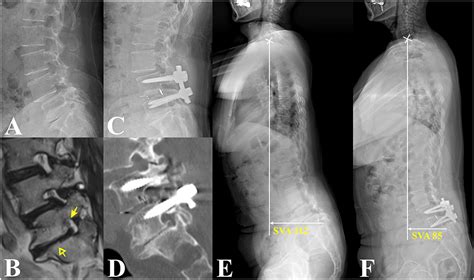

To confirm Severe Bilateral Foraminal Stenosis, medical professionals rely on advanced imaging and clinical evaluation. Physical examinations typically focus on testing reflexes, muscle strength, and dermatomal sensitivity to identify which nerve roots are being compromised. Once a clinical suspicion is formed, imaging is utilized to provide a roadmap of the spinal canal.

The gold standard for diagnosis is an MRI (Magnetic Resonance Imaging) scan. Unlike X-rays, which only show bone, an MRI provides a detailed cross-sectional view of soft tissues, nerves, and discs. It allows the surgeon to visualize the exact degree of narrowing at each level of the spine. In cases where an MRI is not possible, a CT myelogram may be used to see how the spinal fluid flows around the nerves.

When conservative methods fail to provide adequate pain relief or when there is progressive neurological deficit (loss of strength or reflex), surgery may be recommended. The goal of surgery is decompression—physically removing the bone spurs or disc material that is squeezing the nerve. Modern techniques like micro-decompression or minimally invasive lumbar decompression (MILD) allow surgeons to clear the foraminal path with smaller incisions, less muscle damage, and faster recovery times.